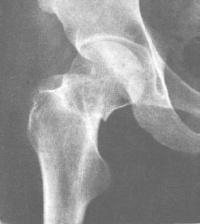

影像学表现[编辑 | 编辑源代码]

按股骨颈骨折部的形态分为嵌入型和错位型骨折。这两型股骨颈骨折的骨折线可表现为致密线和/或透亮线。致密骨折线表示两骨折端的骨小梁有重叠嵌插,而透亮骨折线则意味着两骨折端有分离。

嵌入型股骨颈骨折无明显错位,通常股骨颈可见模糊的致密骨折线,局部骨小梁中断,局部骨皮质出现小的成角或凹陷,股骨干的外旋畸形小明显。此型骨折属较稳定性骨折。由于骨折发生时外力作用的不同,股骨头可发生不同程度的内收、外旋。前倾或后倾的成角畸形。如出现嵌入端成角畸形较明显,或骨折线的斜度较大、骨折端部分有分离,或股骨干外旋明显时,提示骨折不稳定。

错位型股骨颈骨折较常见,亦称为内收型股骨颈骨折。两折端出现旋转和错位。股骨头向后倾骨折端向前成角,股骨干外旋向上错位,骨折线分离明显。

另外,接骨折部位又可分型为:头下型:骨折线位于头颈交界处;经颈型:骨折线位于股骨颈的中段;基底型:骨折线位于股骨颈底部,大部分位于关节囊外;头颈型:骨折线上端在头下,下端在股骨颈的中部,此型骨折近端的血供不好,不易愈合。